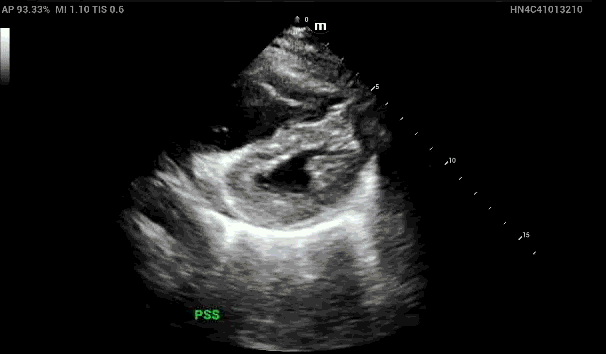

In the apical 4 chamber view, again demonstrated is the dilated right heart concerning for right heart strain.

When looking at the Apical Four Chamber view, how can you confirm that you’re actually looking at the RV and don’t have the probe marker flipped?

1. Tricuspid valve tends to be more near field than the mitral valve

2. Moderator band may be seen in the right ventricle

3. In the apical 5 chamber view, can see the LVOT located in the LV